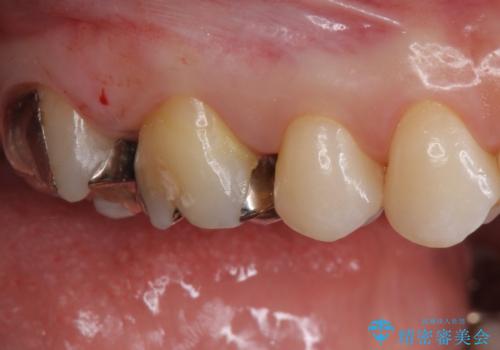

- 銀歯を白くしたいとのことで来院されました。

詰め物が覆っている面積が大きいため、強度を考慮してセラミックインレーではなくクラウンでの修復処置を進めていきます。

- 右上67 仮歯+ジルコニアクラウン:11,000円×2+121,000円×2 費用は治療当時の料金となります